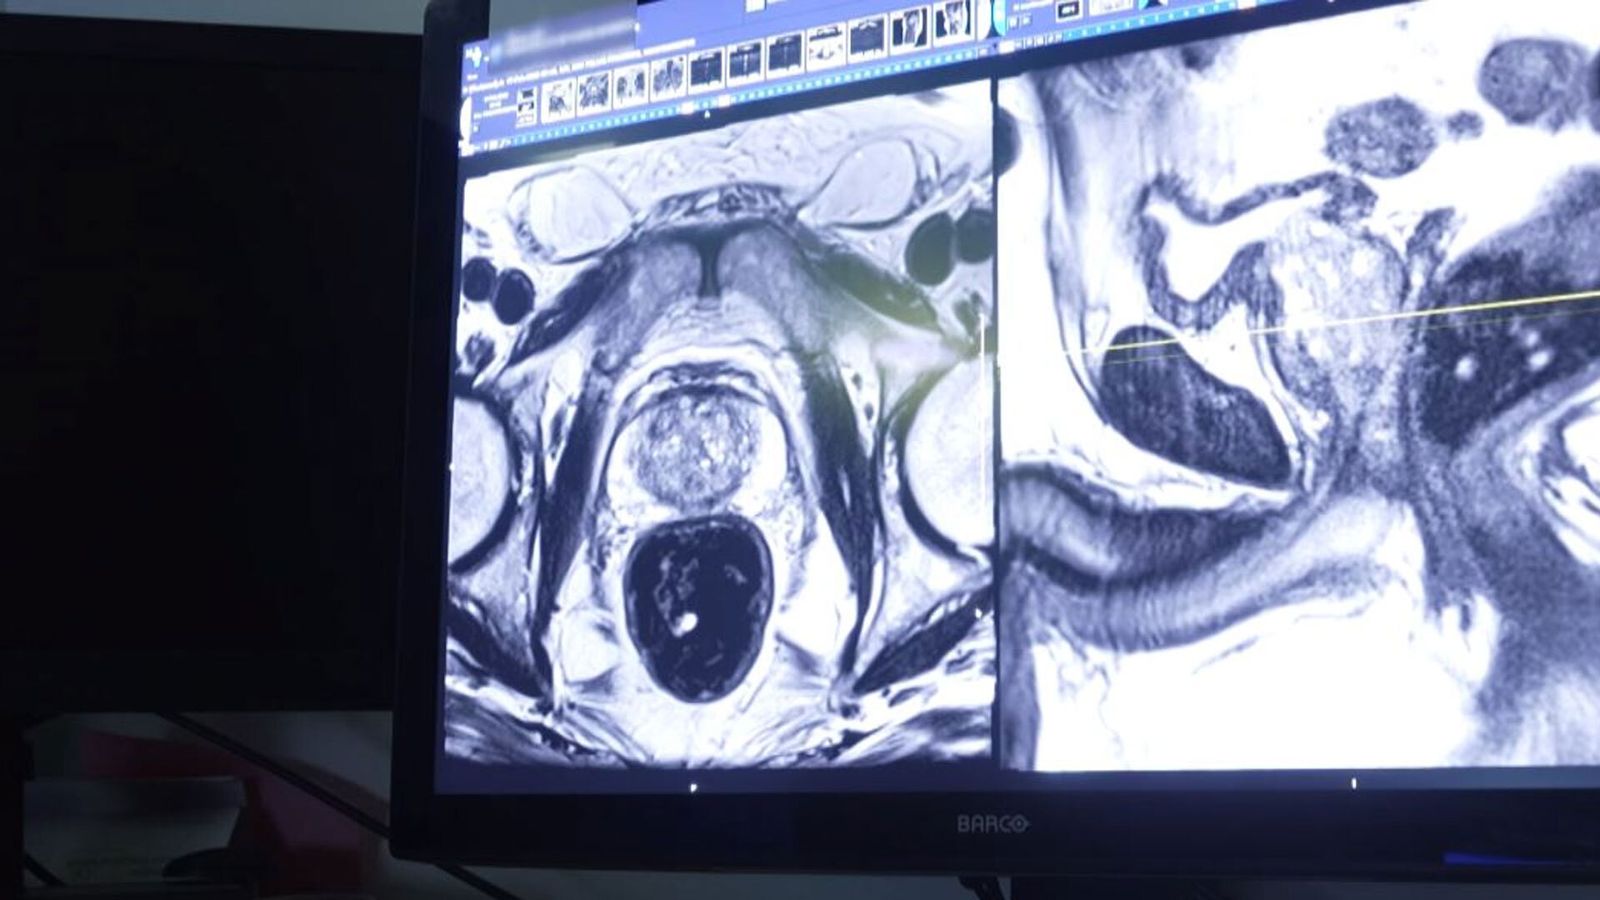

Les méthodes de dépistage

Le dépistage du cancer de la prostate peut inclure plusieurs méthodes, parmi lesquelles :

– **Test de l’antigène spécifique de la prostate (PSA)** : Un test sanguin qui mesure le niveau de PSA, une protéine produite par la prostate. Des niveaux élevés peuvent indiquer un cancer, mais peuvent également être causés par d’autres conditions.

– **Examen digital rectal (EDR)** : Un examen physique effectué par un médecin pour évaluer la taille et la consistance de la prostate.

– **Biopsie** : Si les tests précédents indiquent un risque, une biopsie peut être réalisée pour confirmer la présence de cellules cancéreuses.

Ces méthodes sont souvent utilisées en combinaison pour fournir une évaluation précise du risque de cancer.